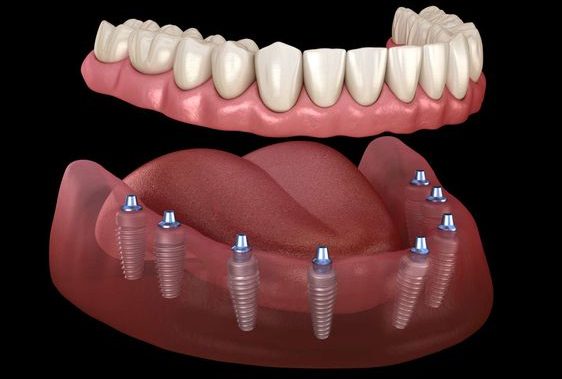

All-on-6 Dental Implants

Start from £ 3850

Timescale 7 days

Digital Precision and Specialization: Because Antalya is a global hub for dental tourism, our surgeons perform high-complexity restorations, such as “All-on-4” and full-mouth rehabilitations, at a much higher frequency than the average local dentist in London or New York. We utilize 3D Tomography and digital smile design to create a precise “blueprint” of your jaw, ensuring a level of surgical accuracy that minimizes trauma and accelerates biological healing.

Dental implants in Antalya represent the perfect intersection of advanced medical technology and world-class hospitality. At Hair Legends, we define a dental implant not just as a replacement tooth, but as a sophisticated architectural restoration of your facial structure. This procedure involves placing a biocompatible titanium or ceramic post into the jawbone, which acts as a permanent root to support a handcrafted crown.

Choosing Antalya for this transformation allows you to access elite tier Swiss and German implant systems at a fraction of Western costs, managed within a boutique ecosystem. Our approach focuses on biological healing; by combining surgical mastery with premium logistics and secluded luxury stays, we ensure your implants integrate seamlessly. In Antalya, a dental implant is more than a clinical treatment it is a stress-free journey toward a permanent, natural, and legendary smile.